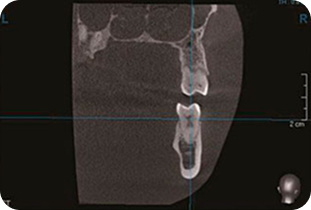

Точная диагностика - залог успешного лечения

Почувствуйте разницу между понорамным снимком и 3D томографией.

Панорамный снимок

На панорамном снимке видно, что изменения и заболевания на беспокоящих зубах отсутствуют.

Компьютерная 3д томография

На компьютерной томографии видно, что начал развиваться гайморит, вызванный заболеванием зубов, образовавшимися кистами.